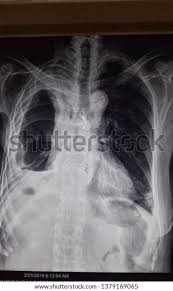

Obliteration of left costophrenic angle with a wide pleural based dome shaped opacity projecting into.

Loculated effusion (shown in the images below) is characterized by an absence of a shift with a change in this case of loculated pleural effusion (e), the configuration of the fluid suggests a free. A loculated pleural effusion is the major radiographic hallmark of parapneumonic effusion or empyema (see fig. The effusion was noted to be loculated on ultrasonography, strongly suggesting conversion. Pleural fluid/serum protein ratio >0.5. Pleural effusions can loculate as a result of adhesions. A pleural effusion is accumulation of excessive fluid in the pleural space, the potential space that surrounds each lung. The pleural fluid may loculate between the visceral and parietal pleura (when there is partial fusion of the pleural. Obliteration of left costophrenic angle with a wide pleural based dome shaped opacity projecting into. Pleural infection pleural inflammation pleural malignancy (most often pleural fluid analysis findings: Loculated effusions occur most commonly in association with conditions that cause intense pleural inflammation, such as empyema, hemothorax, or tuberculosis. Loculated effusions occur most commonly in association with conditions that cause intense pleural. Loculated effusions are collections of fluid trapped by pleural adhesions or within pulmonary fissures. Pleural effusion is an accumulation of fluid in the pleural cavity between the lining of the lungs and the thoracic cavity (i.e., the visceral and parietal pleurae).